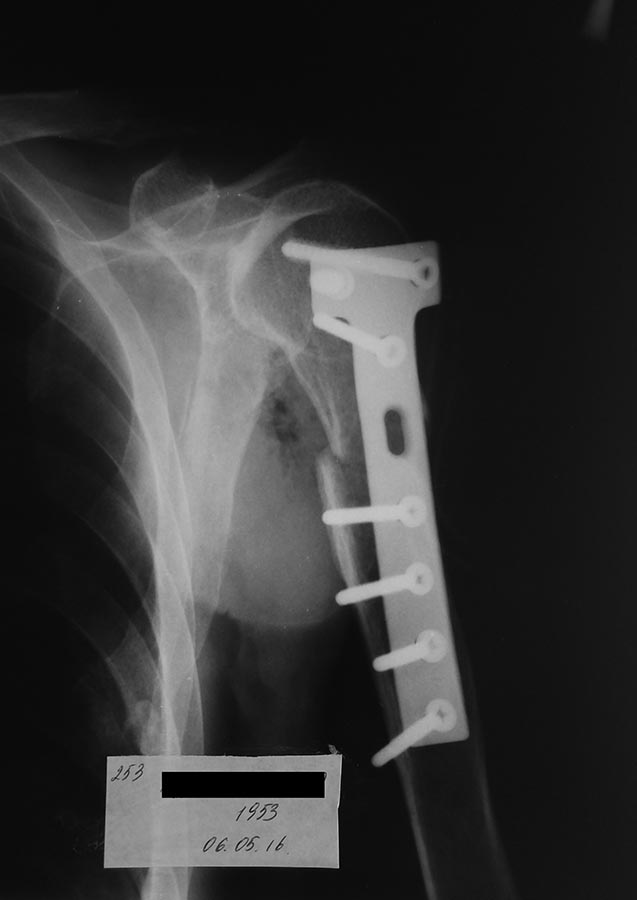

Это диафизарный перелом, а не хирургической шейки. Гематомы... Ну бывает. Пульс-то на лучевой артерии есть? Неврологические нарушения?

Если пластина "лист клевера" - это все. что доступно, ну ей сделайте. Попробуйте сделать контроль, может, получше положение отломков стало, и, возникнут мысли про ведение без операции?

Всем спасибо.

Операция получилось удачно. При ревизии обнаружклось повреждение дельтовидной мышчы с дистальным отломком плечевой кости.

Только много время ушла на репозицию

Пришлось фиксировать Т образной пластиной